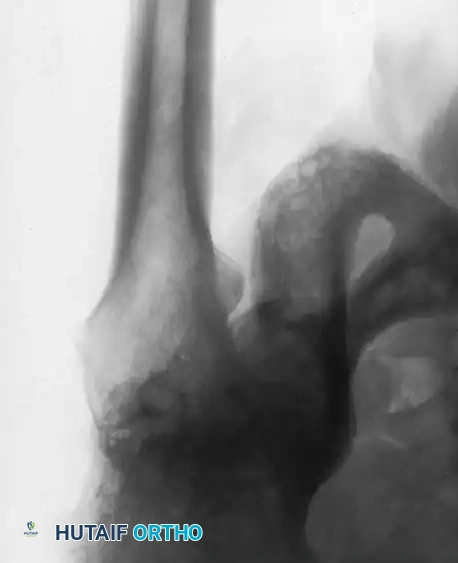

Fig. 7-73 Inadequate deepening of acetabulum. A and B, Degenerative arthritis with intraarticular osteophyte formation and lateral subluxation. Medial osteophytes were not removed, and socket remains in lateralized position. Superior coverage is provided only by large osteophyte.

Failure to medialize the acetabulum leaves the superior portion of the cup unsupported or resting on structurally inferior osteophytic bone rather than the solid iliac column. Furthermore, careful excision of all peripheral acetabular osteophytes is mandatory to prevent postoperative bony impingement, which can lead to decreased range of motion, accelerated polyethylene wear, and instability.